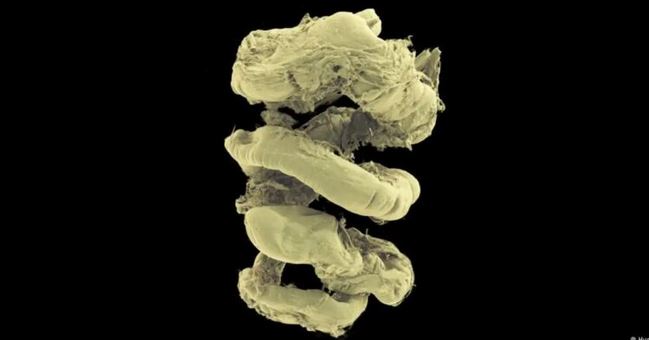

El Atlas de Órganos Humanos, creado mediante un potente método de imagen sincrotrón, reúne algunas de las instantáneas 3D más detalladas de órganos jamás producidas y proporciona una nueva forma de comprender la anatomía y las enfermedades.

Esto permite a los investigadores escanear órganos humanos ex vivo intactos de forma no destructiva y luego ampliar la imagen hasta una resolución casi celular (menos de una micra, 50 veces más fina que el grosor de un cabello humano).

Ofrece, escriben en su artículo, “una exploración integral de la anatomía humana, proporcionando una perspectiva inigualable de las estructuras complejas y sus relaciones espaciales“.